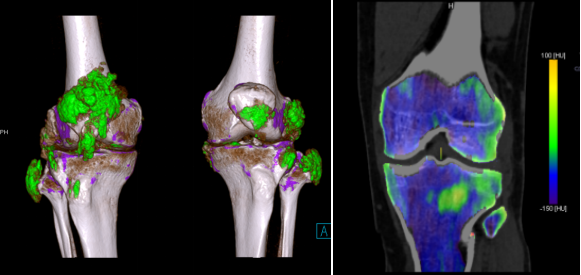

高能谱分离度!配备业界独有的双源双能量成像技术及能谱纯化系统,能够精准识别碘、水、脂肪等多种物质成分,并开展精细化定量分析,为病变性质判断提供客观数据支撑。

泌尿系统检查:精准分析结石成分,指导个体化治疗可准确鉴别尿路结石的化学成分,明确结石类型,为医生制定针对性的排石、溶石治疗方案提供关键参考,提高治疗效率。